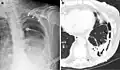

A fibrothorax can typically be diagnosed by taking an appropriate medical history in combination with the use of appropriate imaging techniques such as a plain chest X-ray or CT scan.[3] These imaging techniques can detect fibrothorax and pleural thickening that surround the lungs.[7] The presence of a thickened peel with or without calcification are common features of fibrothorax when imaged.[3] CT scans can more readily differentiate whether pleural thickening is due to extra fat deposition or true pleural thickening than X-rays.[3]

If a fibrothorax is severe, the thickening may restrict the lung on the affected side causing a loss of lung volume.[7] Additionally, the mediastinum may be physically shifted toward the affected side.[3] A reduction in the size of one side of the chest (hemithorax) on an X-ray or CT scan of the chest suggests chronic scarring.[6] Signs of the underlying disease causing the fibrothorax are also occasionally seen on the X-ray.[6] A CT scan may show features similar to those seen on a plain X-ray.[7] Lung function testing typically demonstrates findings consistent with restrictive lung disease.[6]

Extensive left-sided fibrothorax

Chest radiograph displaying inhomogeneous opacification of the left half of the chest that is fibrothorax